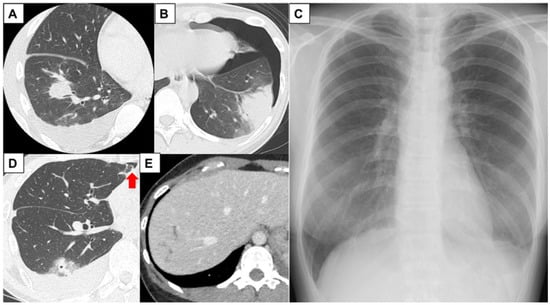

| Radiographic and CT findings | |||||

| Intrapulmonary lesion | Nodular lesion | Infiltration | − | Nodular lesion | − |

| Pleural lesion | Pleural effusion | Pleural effusion Pneumothorax | Pleural effusion Pneumothorax | Pleural effusion Pneumothorax | Pleural effusion |

| Intraperitoneal lesion | Ascites | − | − | − | Linear low attenuation area of the liver |